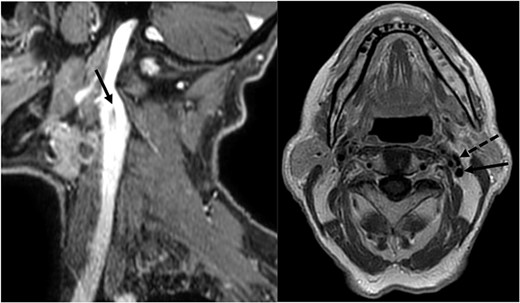

A 78-year-old man with a follow-up PET for a Type B mantle cell lymphoma finding of uptake in in the epiglottis and left laterocervical region is reported here. The patient was diagnosed with squamous cell carcinoma (SCC) after fine needle aspiration of an adenopathy at Level II. His workup included an MRI of the neck with contrast enhancement, which revealed laterocervical lymphadenopathy (bilateral level IIa and left Level III with the biggest adenopathy with maximum diameter of 12 × 12 mm) and thickening of the epiglottis extended at the floor of the left vallecula. No mention was made of an IJV abnormality in the report even though it was noticed during the preoperative evaluation by the surgeon (Fig. 1). The fibroendoscopic evaluation of the neck showed an asymmetry of the epiglottis with the presence of vegetating tissue at the level of the left lingual border of the epiglottis, preserved motility of the vocal cords, and normal breathing space. The patient’s clinical stadiation was cT2 N2c M0. The multidisciplinary meeting indicated an endoscopic partial laryngectomy and bilateral laterocervical dissection. The cervical lymph node dissection on the left side discovered a duplication of the IJV which resulted dilated in comparison to the IJV on the right side. The SAN passed medially to the anterior vein and laterally to the posterior vein. Both the IJV and the SAN were preserved during the procedure (Fig. 2).

SAN passes through medially to the anterior part (filled triangle) and laterally to the posterior part (star) of the fenestrated IJV (arrowhead); ICA: internal carotid artery; SCM: sternocleidomastoid muscle.